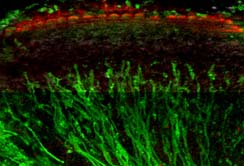

Innsbruck, 23.01.2012: In der Europäischen Union leben rund 44 Millionen Menschen mit einer Hörschädigung. Weltweit sind es annähernd 250 Millionen. Bis 2050 könnte die Anzahl der weltweit Betroffenen allerdings auf über 900 Millionen steigen, schätzt die WHO. Bisher sind viele Hörbeeinträchtigungen nicht therapierbar: Das Innenohr ist ein geschlossenes und schwer zugängliches Organ. „Schäden am Innenohr sind deshalb zur Zeit nur beschränkt therapierbar“, erklären Prof.in Anneliese Schrott-Fischer und Dr. Rudolf Glückert vom Forschungslabor für Innenohrbiologie der Innsbrucker HNO-Klinik. Durch die Zusammenarbeit von wissenschaftlichen und industriellen Partnern aus elf verschiedenen Ländern in dem Projekt „Nanoear“ konnten nun aber Nanopartikel entwickelt werden, die als Träger für Medikamente oder therapeutische DNA dienen. Diese können also gezielt an bestimmte Zellen ins Innenohr transportiert und dort freigesetzt werden. „Verwendet werden dafür Nanopartikel der dritten Generation, die in der Lage sind, verschiedene Moleküle aufzunehmen“, erklärt Prof.in Schrott-Fischer. „Noch sind die Partikel allerdings in einem Stadium, in dem sie nicht an Patient:innen angewendet werden können. Aber mit dem Projekt haben wir den Grundstock dafür gelegt, dass die Partikel weiterentwickelt und auch in der Praxis eingesetzt werden können.“ Es gibt daher die Hoffnung, mit Hilfe der Nanopartikel eine ganze Bandbreite von vielversprechenden neuen Therapiemöglichkeiten für die Behandlung von Hörbeeinträchtigungen zu entwickeln.

An dem Projekt „Nanoear“ haben insgesamt 14 Universitäten und zehn Firmen aus elf verschiedenen Ländern gearbeitet. Koordiniert wurde die Forschungsarbeit von der Universität Tampere in Finnland. Das von der EU finanzierte Projekt hatte ein Volumen von 10,5 Millionen Euro. Vom Forschungslabor für Innenohrbiologie in Innsbruck waren Dr. Rudolf Glückert, Mag. Christian Pritz, Dr. József Dudás, Dr. Soumen Roy und BMA Mario Bitsche unter der Leitung von Prof.in Schrott-Fischer an dem Projekt beteiligt. „Unser Beitrag war vor allem die Entwicklung eines Invitro-Modells, mit dem die entwickelten Nanopartikel an Zellen und Organkulturen getestet werden konnten“, sagt die Teamleiterin. Dadurch konnte die Auswirkung der Partikel auf das lebende Gewebe erforscht werden.